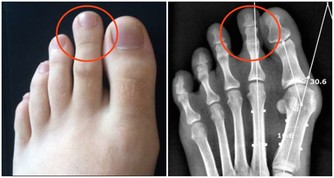

下肢動脈硬化閉塞症小腿抽筋頻繁,還要警惕血管性疾病可能,尤其是老年人。下肢血管硬化時,管腔會變窄,導致局部供血不足、血液循環不暢,組織缺氧及代謝產物蓄積,會使得肢體末端因為缺血出現抽筋、疼痛等不適。如果治療不及時,血管狹窄會逐漸加重,甚至引起外周器官營養缺乏,嚴重時發生壞疽等不良後果。